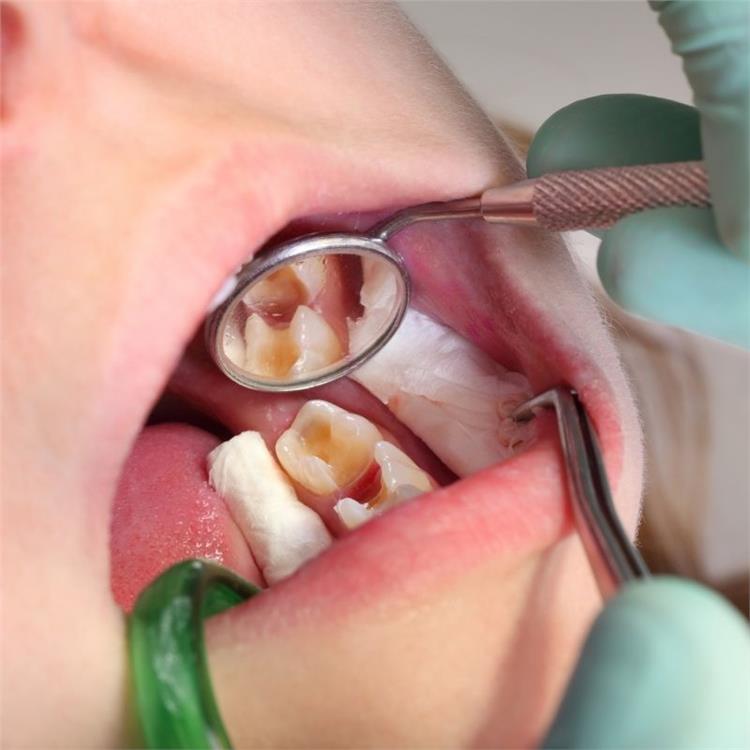

Oral Diagnosis: A Vital Step for Optimal Oral Health

Oral health is an important part of our general health and there is an important process called "Oral Diagnosis" in protecting this health.